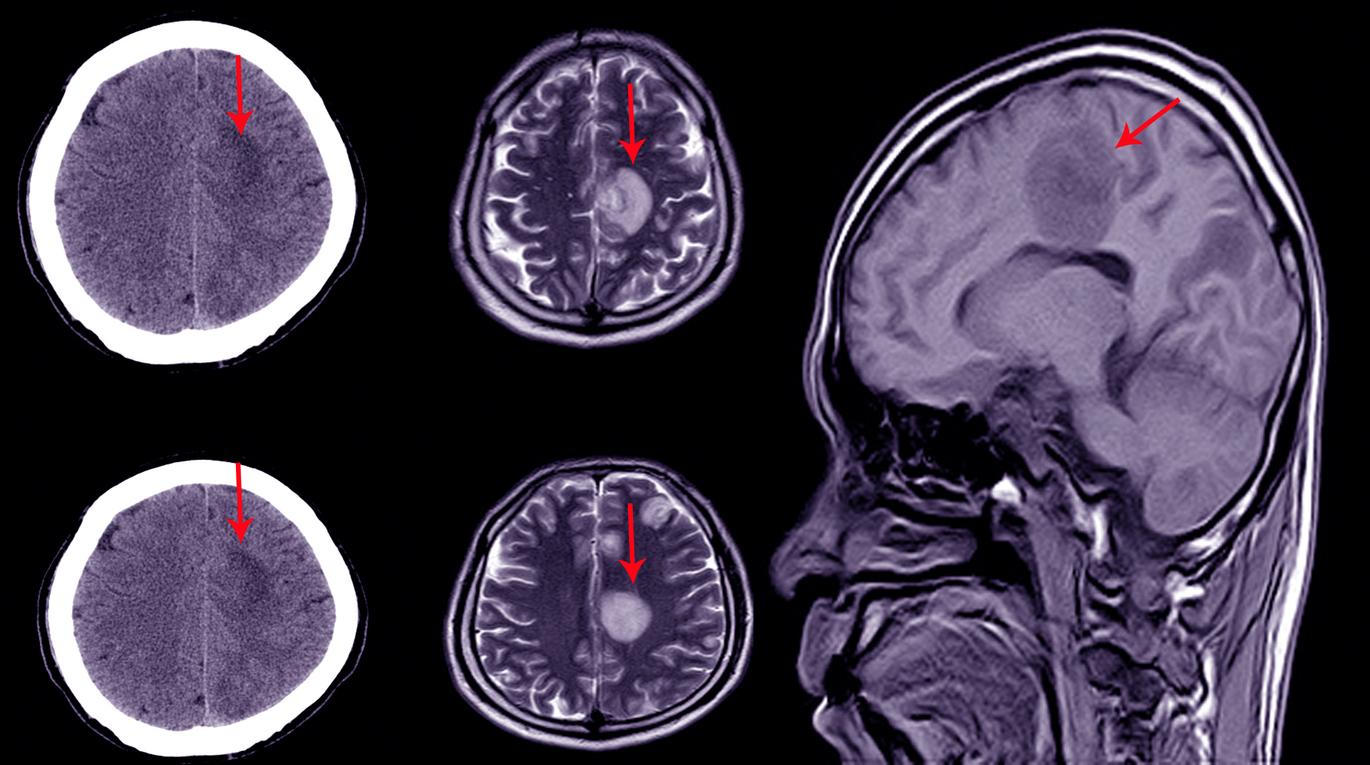

L’hématome sous-dural est généralement consécutif à un choc au crâne (accident, coup, bébé secoué...) ayant provoqué la lésion d’une veine, à l’origine du saignement. Le diagnostic est posé grâce à un scanner ou une IRM cérébrale. Si les petits hématomes ont tendance à se résorber spontanément, les plus importants nécessitent une intervention chirurgicale. En l’occurrence un drainage, qui consiste à percer un trou dans la boîte crânienne pour évacuer l’hématome.